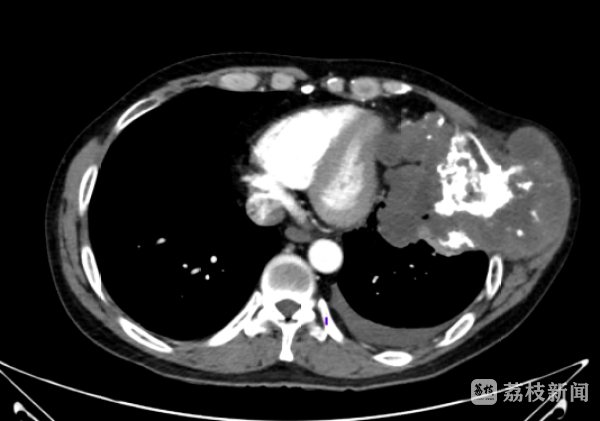

原来,20年前,李先生左侧胸口处就出现这一皮下肿物,直径约2cm,当时未予重视。近两年,患者自觉肿块较前增大,在当地医院就诊,查胸部CT提示:肿块大小约13*9.8*13cm,且对心脏有压迫,与膈肌分界不清。

心胸外科刘宏副主任医师接诊后,考虑该肿瘤起源于肋骨,虽穿刺病理提示软骨性肿瘤(一种良性肿瘤),但CT来看不排除恶性可能,穿刺存在取材不够误诊可能。且肿瘤体积较大,外侵周围脏器及组织可能,建议再次行胸壁肿物穿刺活检,如药物可控,可药物治疗待肿瘤缩小控制后完全切除。

经过充分沟通,刘主任表示,肿瘤本身的巨大,以及已经给心脏带来压迫,与膈肌分界不清,都让手术困难重重。为此,带着患者的信任,刘主任带领团队积极进行术前方案讨论,不断完善,应对术中可能发生的风险。

一切准备就绪后,刘主任认真细致、有条不紊地剥离出这个胸壁巨大肿瘤,肿瘤长径超过17cm,侵及心包、心包前脂肪组织、膈肌,受侵膈肌包块膈面胸膜结节予整块切除,保留膈面腹膜,受侵心包前脂肪组织及心包予切除,游离受侵肋弓,切除肋软骨,整块完整切除肿瘤。予以肿瘤切除后行左膈肌补片修补+胸壁重建术(钛网)。手术顺利完成。